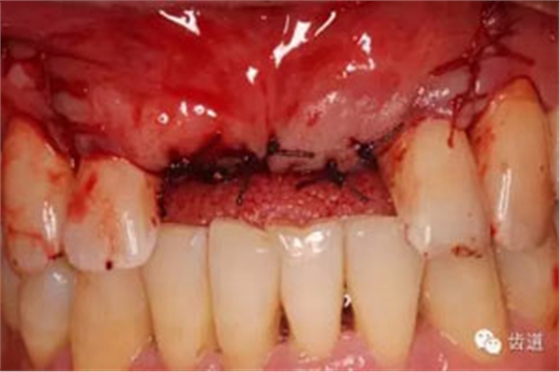

患者對(duì)美觀要求較高,與患者溝通后,擬定采用骨環(huán)技術(shù),同期種植并增加骨寬度和高度。

患者不愿才用自體骨移植,遂建議采用同種異體骨骨塊(皮質(zhì)骨)進(jìn)行骨環(huán)手術(shù)。 種植手術(shù):

骨環(huán)技術(shù)可以解決水平和垂直向的骨不足,但一般采用自體骨。自體骨雖然是骨移植的金標(biāo)準(zhǔn),但是需要在第二術(shù)區(qū)取骨,患者疼苦較大。同種異體骨塊來(lái)自于人類,和自體骨的結(jié)構(gòu)非常類似,成骨性能良好。故筆者選用同種異體骨塊進(jìn)行骨環(huán)手術(shù),在國(guó)內(nèi)外都是首次。該病例筆者隨訪觀察了一年,目前骨環(huán)比較穩(wěn)定。 白石 男 重慶醫(yī)科大學(xué)附屬口腔醫(yī)院種植科主治醫(yī)師,講師,碩士; 國(guó)際種植協(xié)會(huì)高級(jí)??漆t(yī)師,華西口腔醫(yī)學(xué)院碩士畢業(yè)生; 從事種植外科和種植修復(fù)臨床工作10年; 曾接受系統(tǒng)化種植培訓(xùn),有豐富口腔種植治療經(jīng)驗(yàn),擅長(zhǎng)復(fù)雜種植的設(shè)計(jì)與修復(fù),對(duì)全口種植義齒、種植美學(xué)修復(fù)技術(shù)和常規(guī)精密義齒修復(fù)有較深研究。 參加國(guó)內(nèi)外多次會(huì)議,并屢次獲得病例比賽獎(jiǎng)勵(lì)。